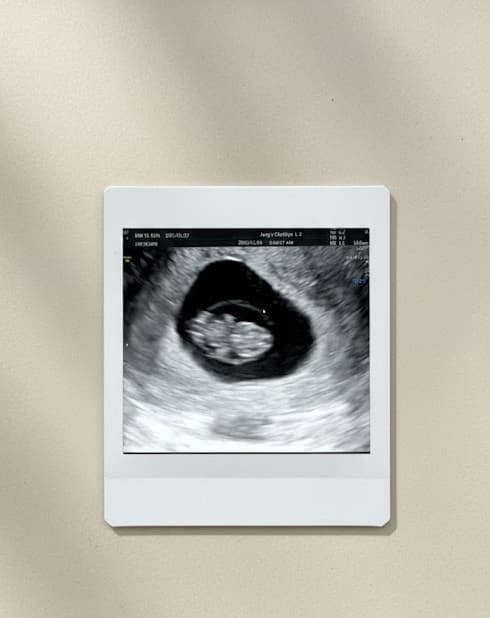

초음파 화면에 작은 점 하나가 보이고.

그 다음 순간,

두근, 두근, 두근.

심장 소리가 들렸다. 0.7cm 밖에 안되는 한 존재가 나에게로 왔다.

그 작은 심장이 이렇게나 힘차게 뛰고 있었다니.

내 안에 심장이 두개가 있다!!🤍